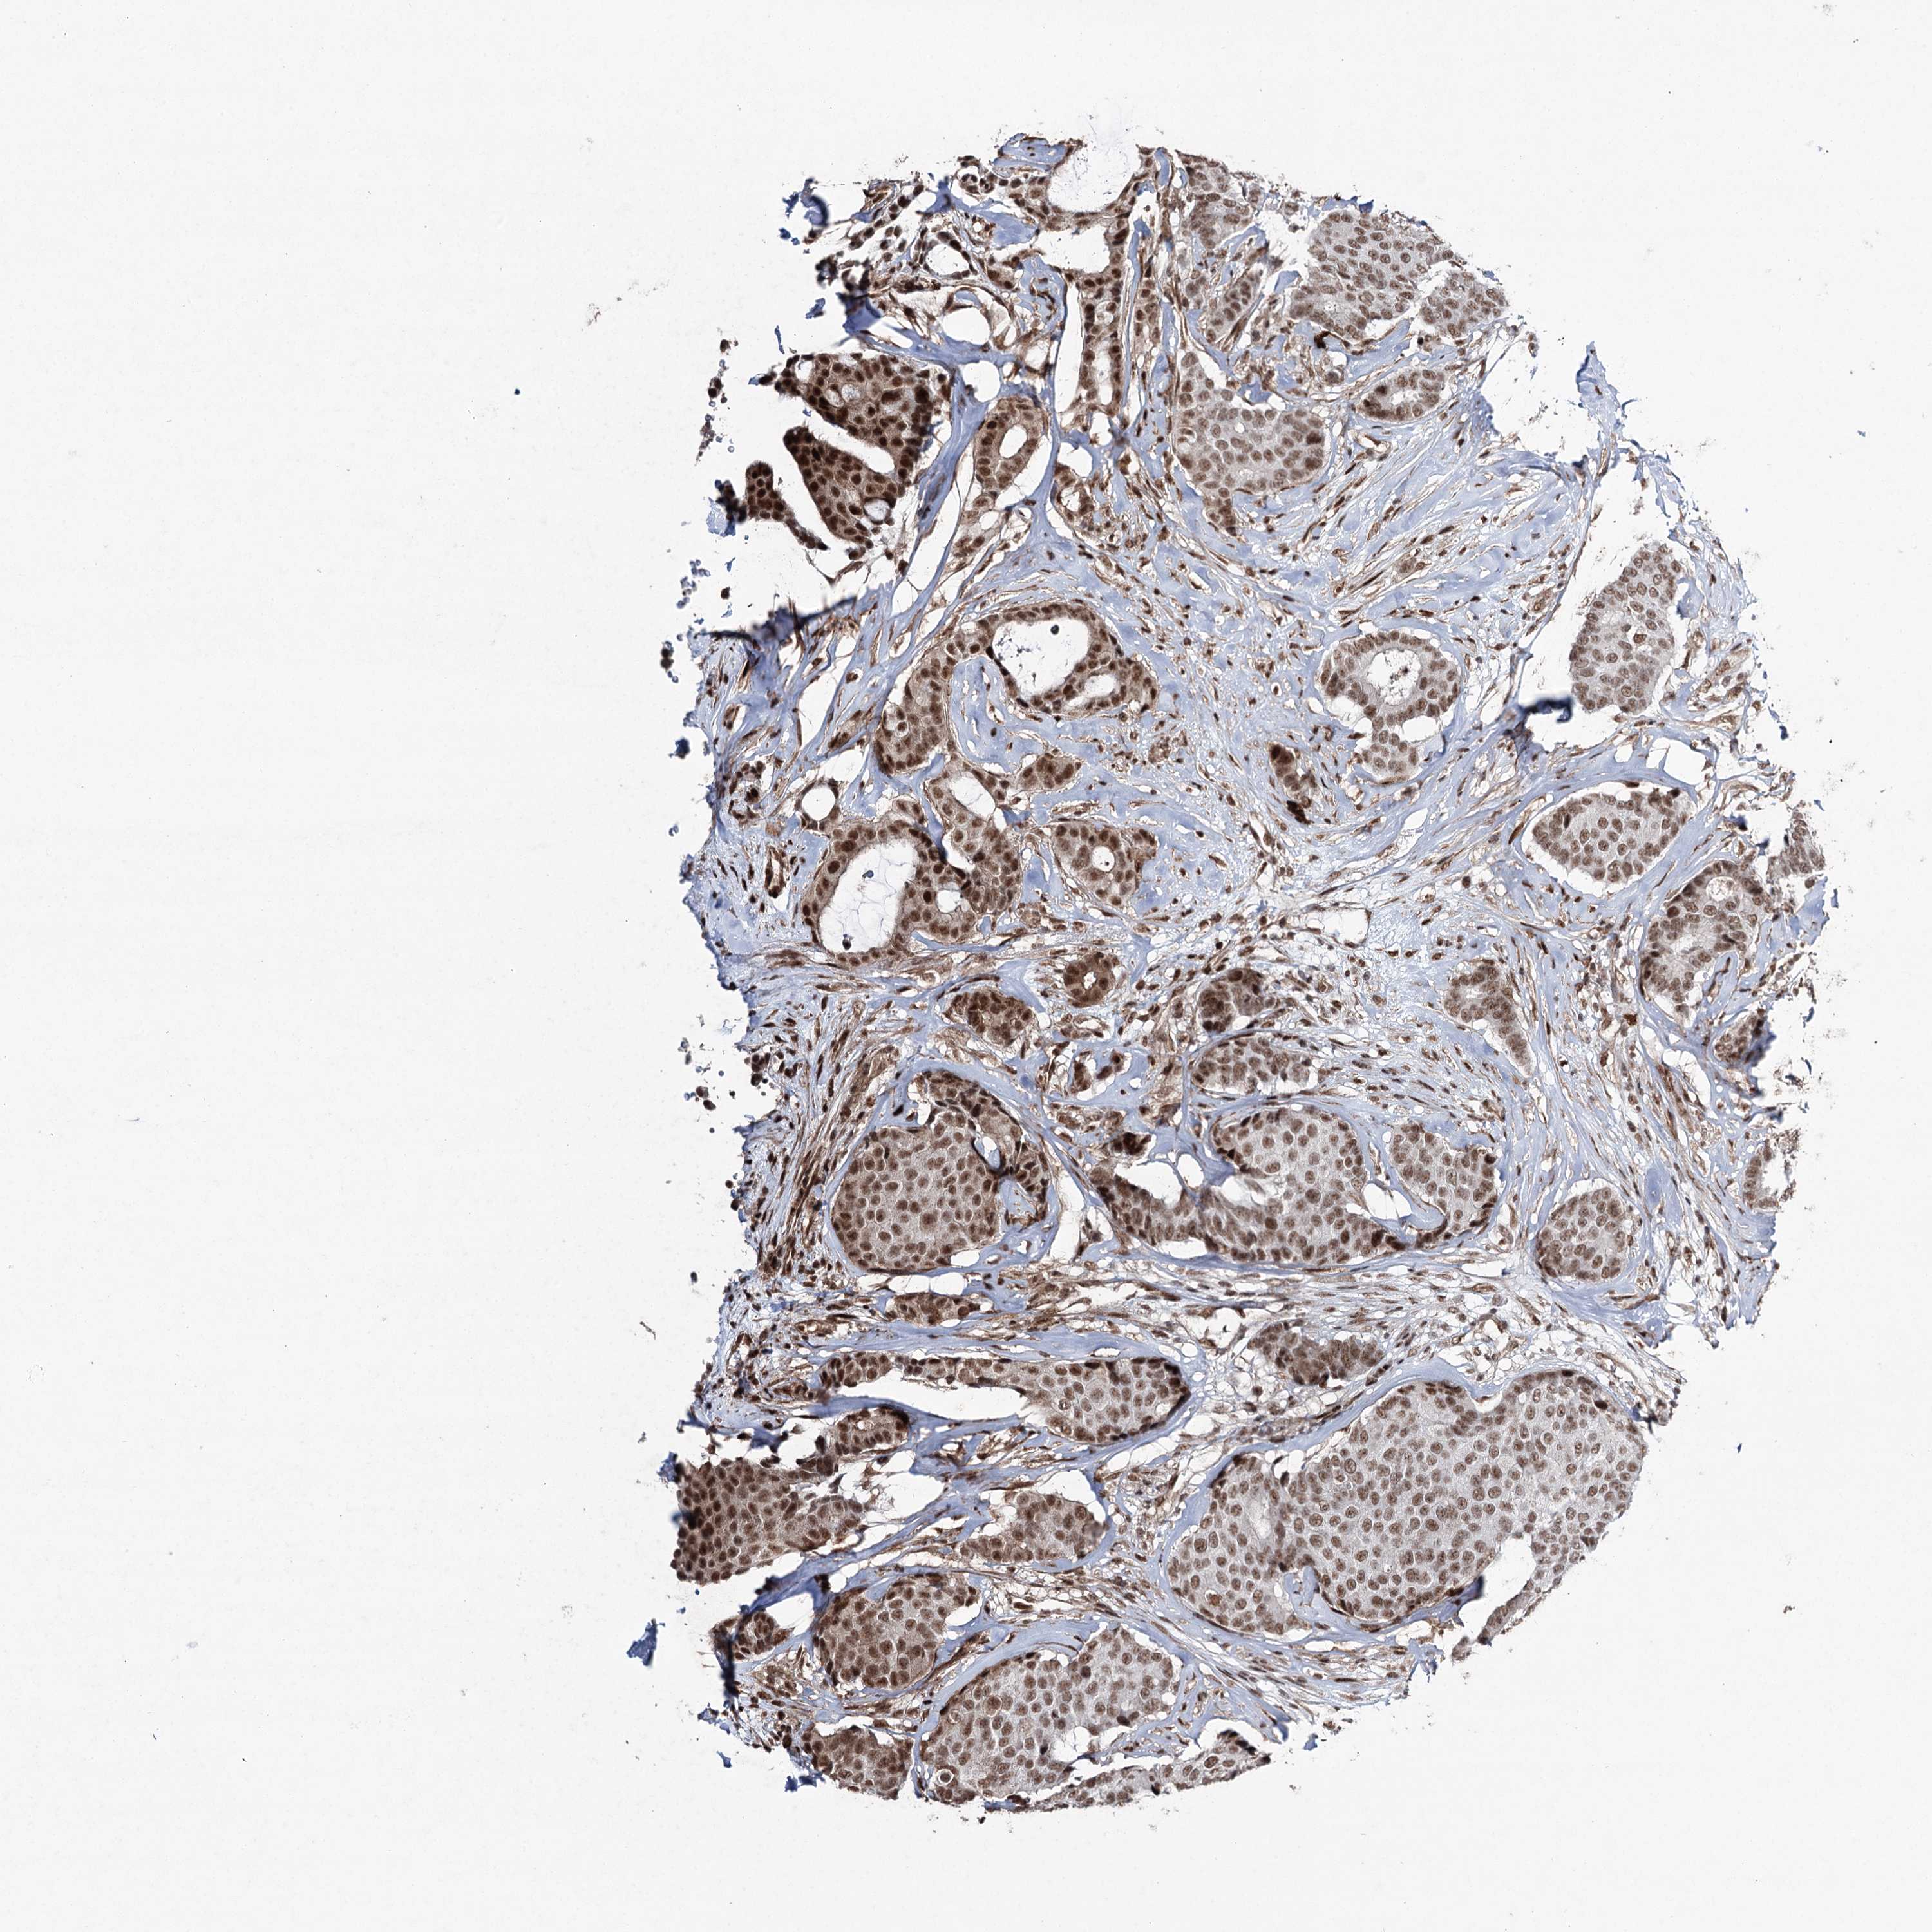

CANCER BREAST CANCER Show tissue menu

BRCA TCGA BRCA VALIDATION PROTEIN EXPRESSION

Breast cancer

Human cancer